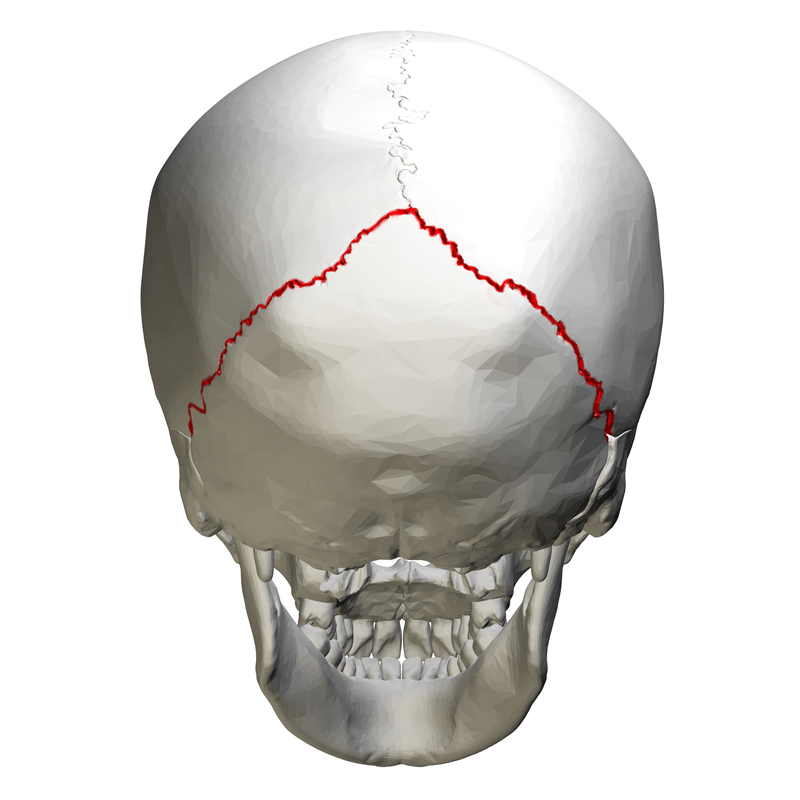

Africanus schrieb:Meine Abbildung zeigt, an welcher Stelle des Schädels der "occipital bone" tatsächlich liegt, während Deine Abbildung den Anschein entstehen lässt, dass dieser höher am Schädel liege. Das nenne ich manipulativ.

Africanus schrieb:Meine Abbildung zeigt, an welcher Stelle des Schädels der "occipital bone" tatsächlich liegt, während Deine Abbildung den Anschein entstehen lässt, dass dieser höher am Schädel liege. Das nenne ich manipulativ.

Deine Quelle:

Wikipedia: Occipital bonevon derselben Quelle.

Vergleiche mit meinem Bild- es gibt keinen Unterschied:

Original anzeigen (0,2 MB)

Original anzeigen (0,2 MB)Dein Manipulationsvorwurf ist also einfach nur lächerlich. Vielleicht lebst du in einer Welt in der zwei räumliche Dimensionen existieren und kannst Darstellungen dreidimensionaler Objekte aus verschiedenen Perspektiven nicht verstehen?

Mach dich nicht lächerlich- wenn es um Perspektive geht, passt meine Darstellung besser zu den Hinterkopffotos als deine.

Ich dachte es würde dich freuen- schließlich ist im Autopsiebericht von der Eintrittswunde im occipitalen Knochen die Rede!